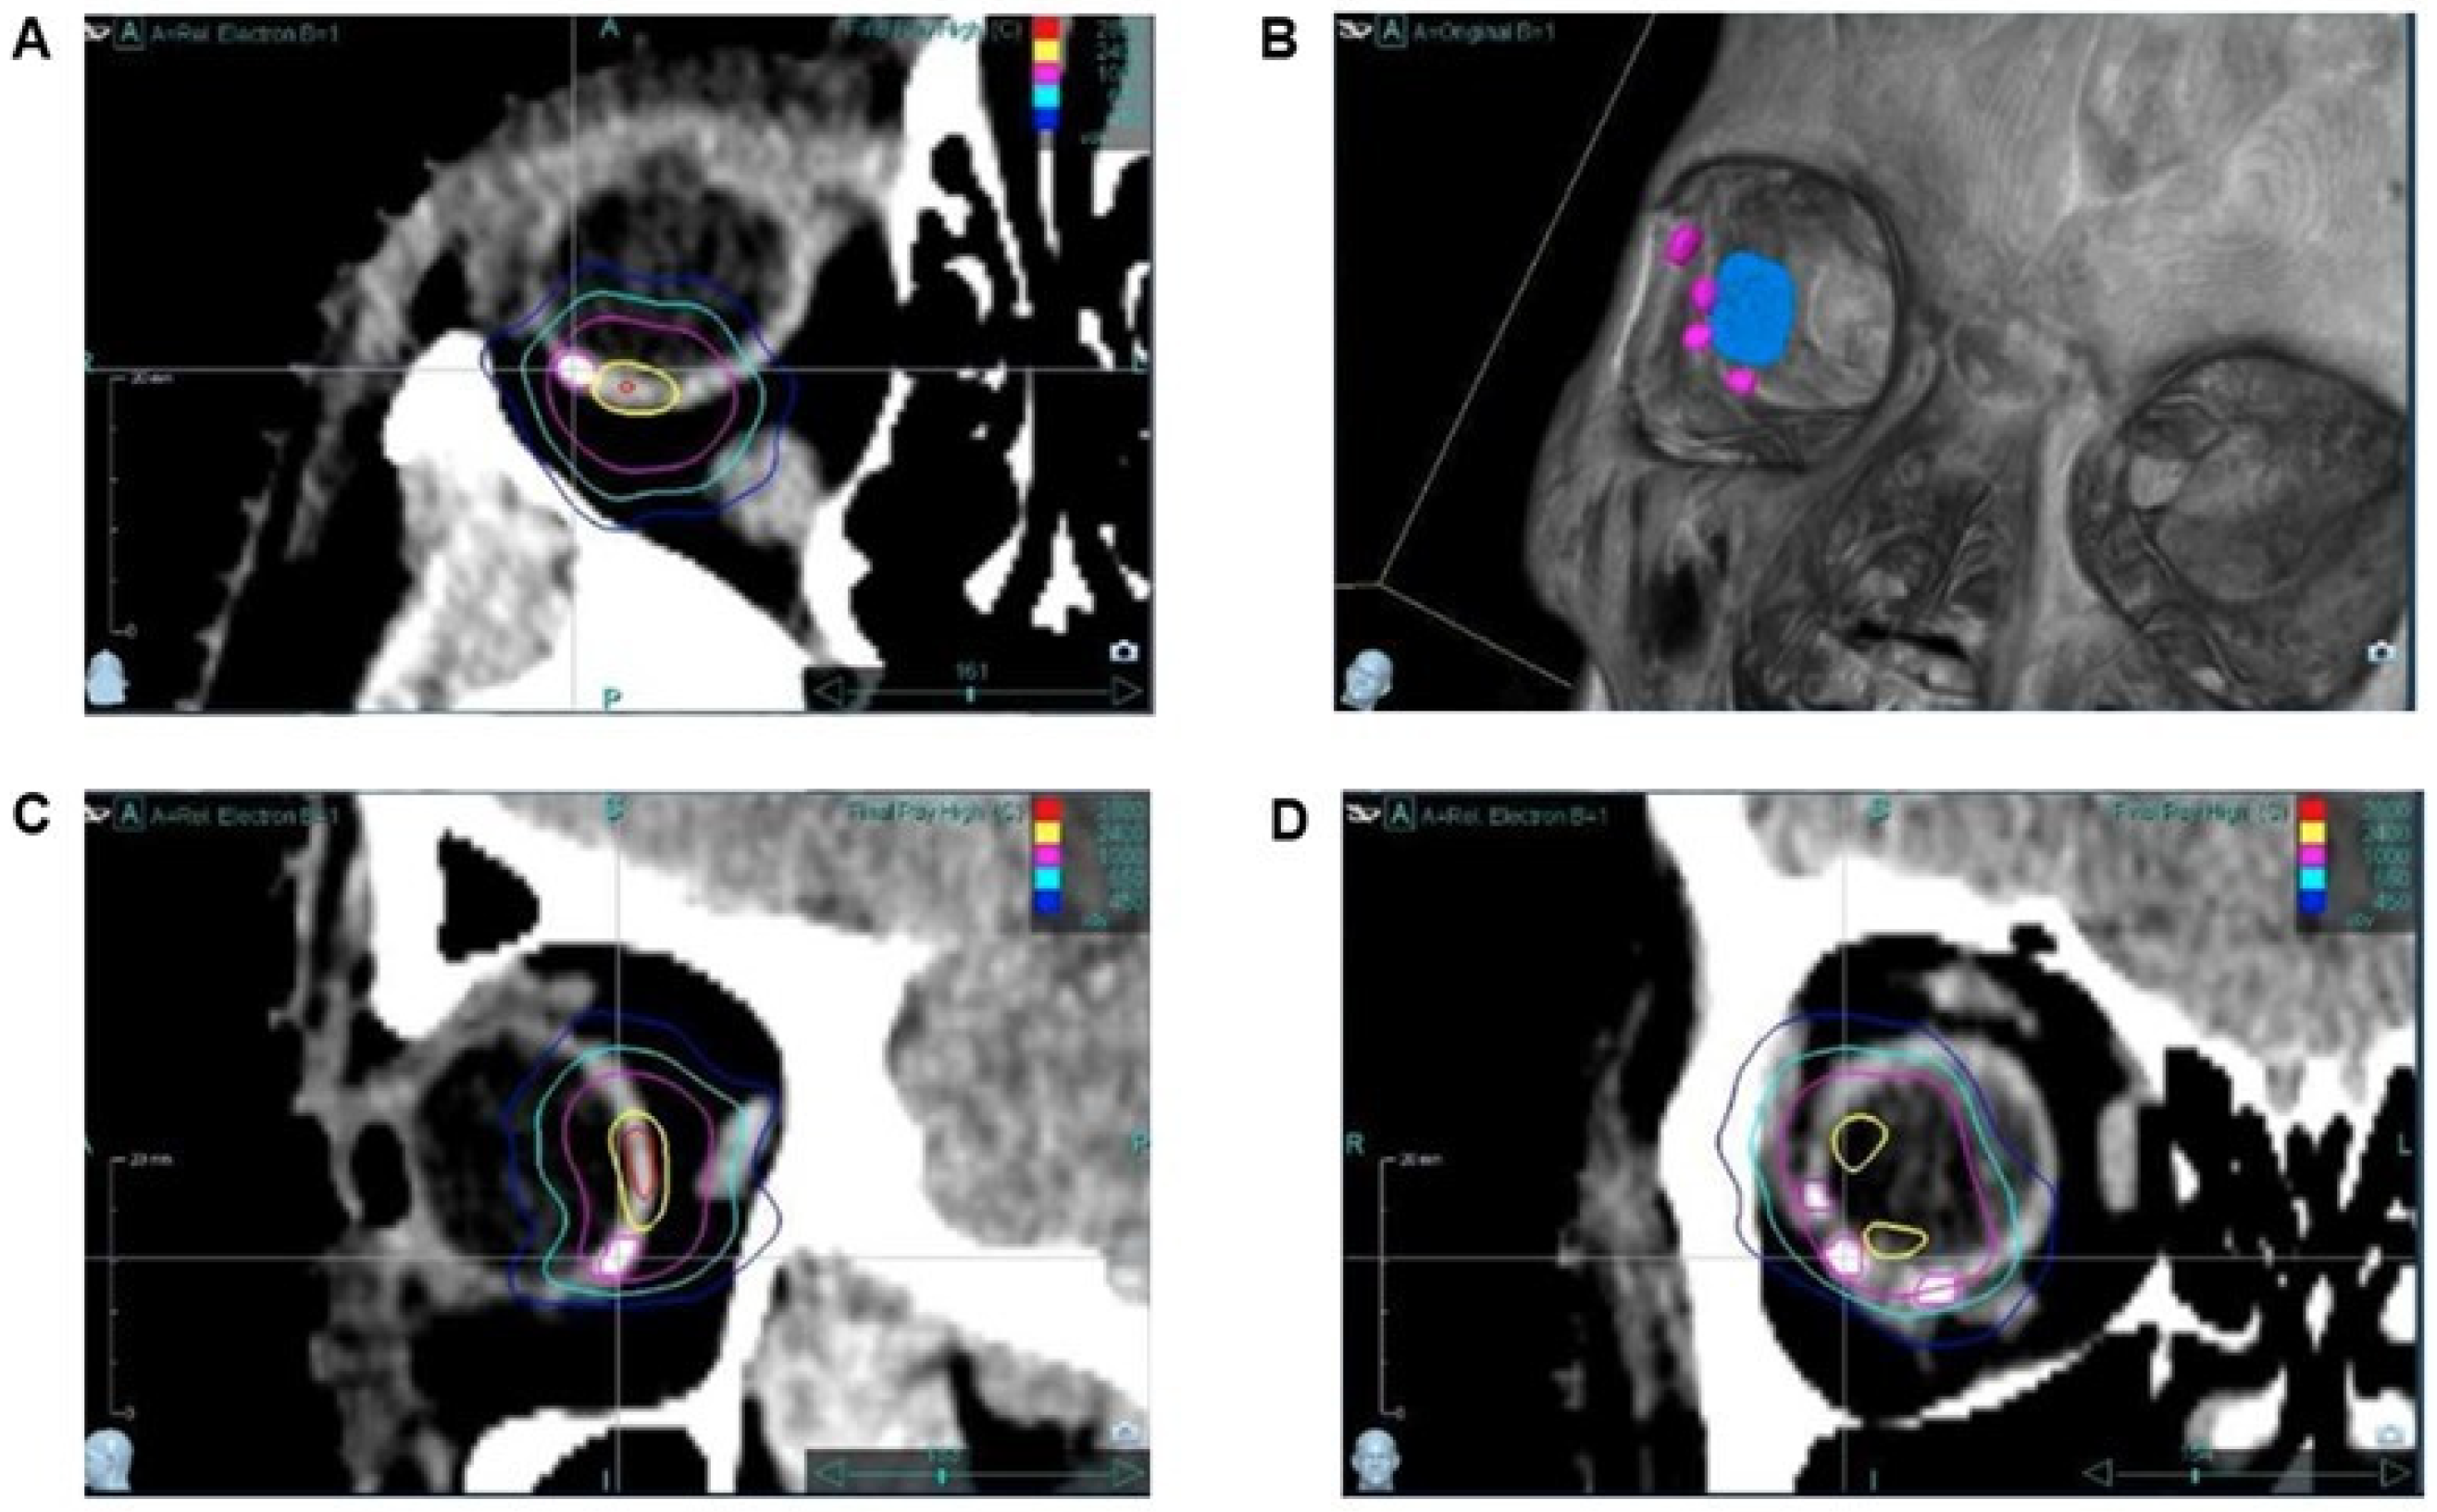

T1-weighted MRI sequences prior to the radiotherapy revealed hypodense areas at the position of the SFM. They were less visible than in the CT scan. In CT, the SFM showed a clear hyperdense signal without any scattering artifacts, which allowed the precise labeling of the target tumor volume (Figure 3). The maximum Hounsfield unit (HU) of the markers ranged from 120 to 140 HU as compared to the corpus vitreum (−10 to +10 HU) and the choroidea (40 to 60 HU) in the CT.

Figure 3.

CT images of the silicone markers ((A) transverse; (C) sagittal; (D) coronal). Image (B) is the result of the VRT (volume rendering technique). Three of the markers were directly placed at the peripheral edges of the tumor, whereas the fourth marker was placed contralaterally. Tumor size (blue) was defined via fundus image, OCT and ultrasonography. In detail, tumor diameters and the distance of the tumor from the optic nerve and the macula measured with the 3 examination techniques were used to determine the tumor boundaries far from the markers. All markers could be clearly detected without scattering artifacts.

Starting with the first patient, we noted a quantum leap in delineation and treatment planning for robotic-guided stereotactic radiosurgery of the choroidal tumor. The clearly visible silicone markers in the CT images immediately enabled more precise target definition and treatment planning. Without scattering artifacts, the precise and fast identification of the marker edges and thus their exact localization were possible (Figure 3). An additional advantage of the new material is the reduced absorption of irradiation. The HU of the markers was only slightly elevated up to 140 HU, whereas TFMs have an HU of about 1500. In addition to artifacts, tantalum markers produce a significant perturbation of the applied dose, since absorption depends on the material density. The quite low material density of silicone significantly improves the dosimetry of radiation therapy treatment.